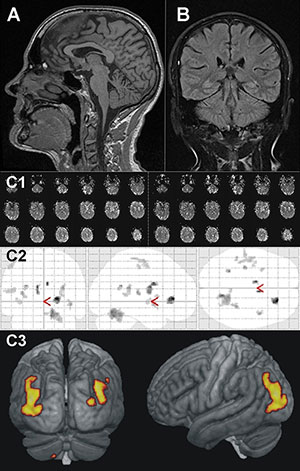

The researchers also looked at how ultramarathon running affects brain volume. Baseline comparison of TEFR participants and controls revealed no significant differences in gray matter volume. At the end of the race, MRI of the brain revealed about a 6.1 percent loss of gray matter volume in the runners. After eight months, gray matter volume had returned to normal levels.

Although the finding on gray matter volume loss while running is astonishing, Dr. Schütz said, it is not cause for alarm.

"Despite substantial changes to brain composition during the catabolic stress of an ultramarathon, we found the differences to be reversible and adaptive," he said. "There is no lasting brain injury in trained athletes participating in ultra-running."